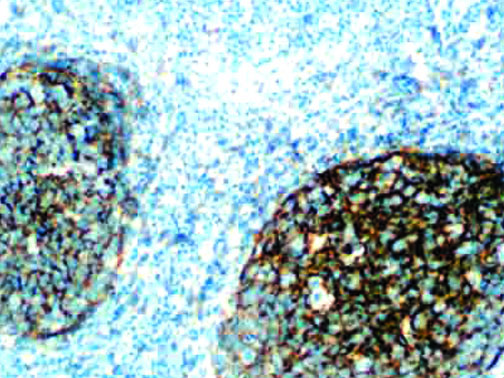

The first cytokines released are interleukin 1β (IL-1β) and tumor necrosis factor-α (TNF-α), which attract a variety of circulating white blood cells (WBCs) to the infection site, including neutrophils, monocytes, macrophages, and natural killer (NK) cells. This response, along with the antipathogenic chemicals released by these cells (i.e., complement), comprise the innate immune response. These cells directly attack the invading pathogen and also release additional cytokines, chief among them interleukin-1 and 6 (IL-6). IL-6 is essential for invoking the adaptive immune response, which calls T-cells, B-cells, and T helper (Th) cells to the infection site. IL-6 also stimulates further recruitment, proliferation and activation of macrophages.

It is the ICU physician who is most likely to witness one of the deadliest manifestations of the abnormal immunological response, the cytokine storm syndrome (CSS). This response is also referred to by some as the cytokine release syndrome (CRS). CSS is characterized by continuous activation and expansion of macrophage and lymphocyte populations, which secrete large amounts of cytokines, causing the cytokine storm. This massive cytokine release is akin to hemophagocytic lymphohistiocytosis (HLH) disease, a syndrome characterized by initial unchecked and persistent activation of cytotoxic T lymphocytes and NK cells.